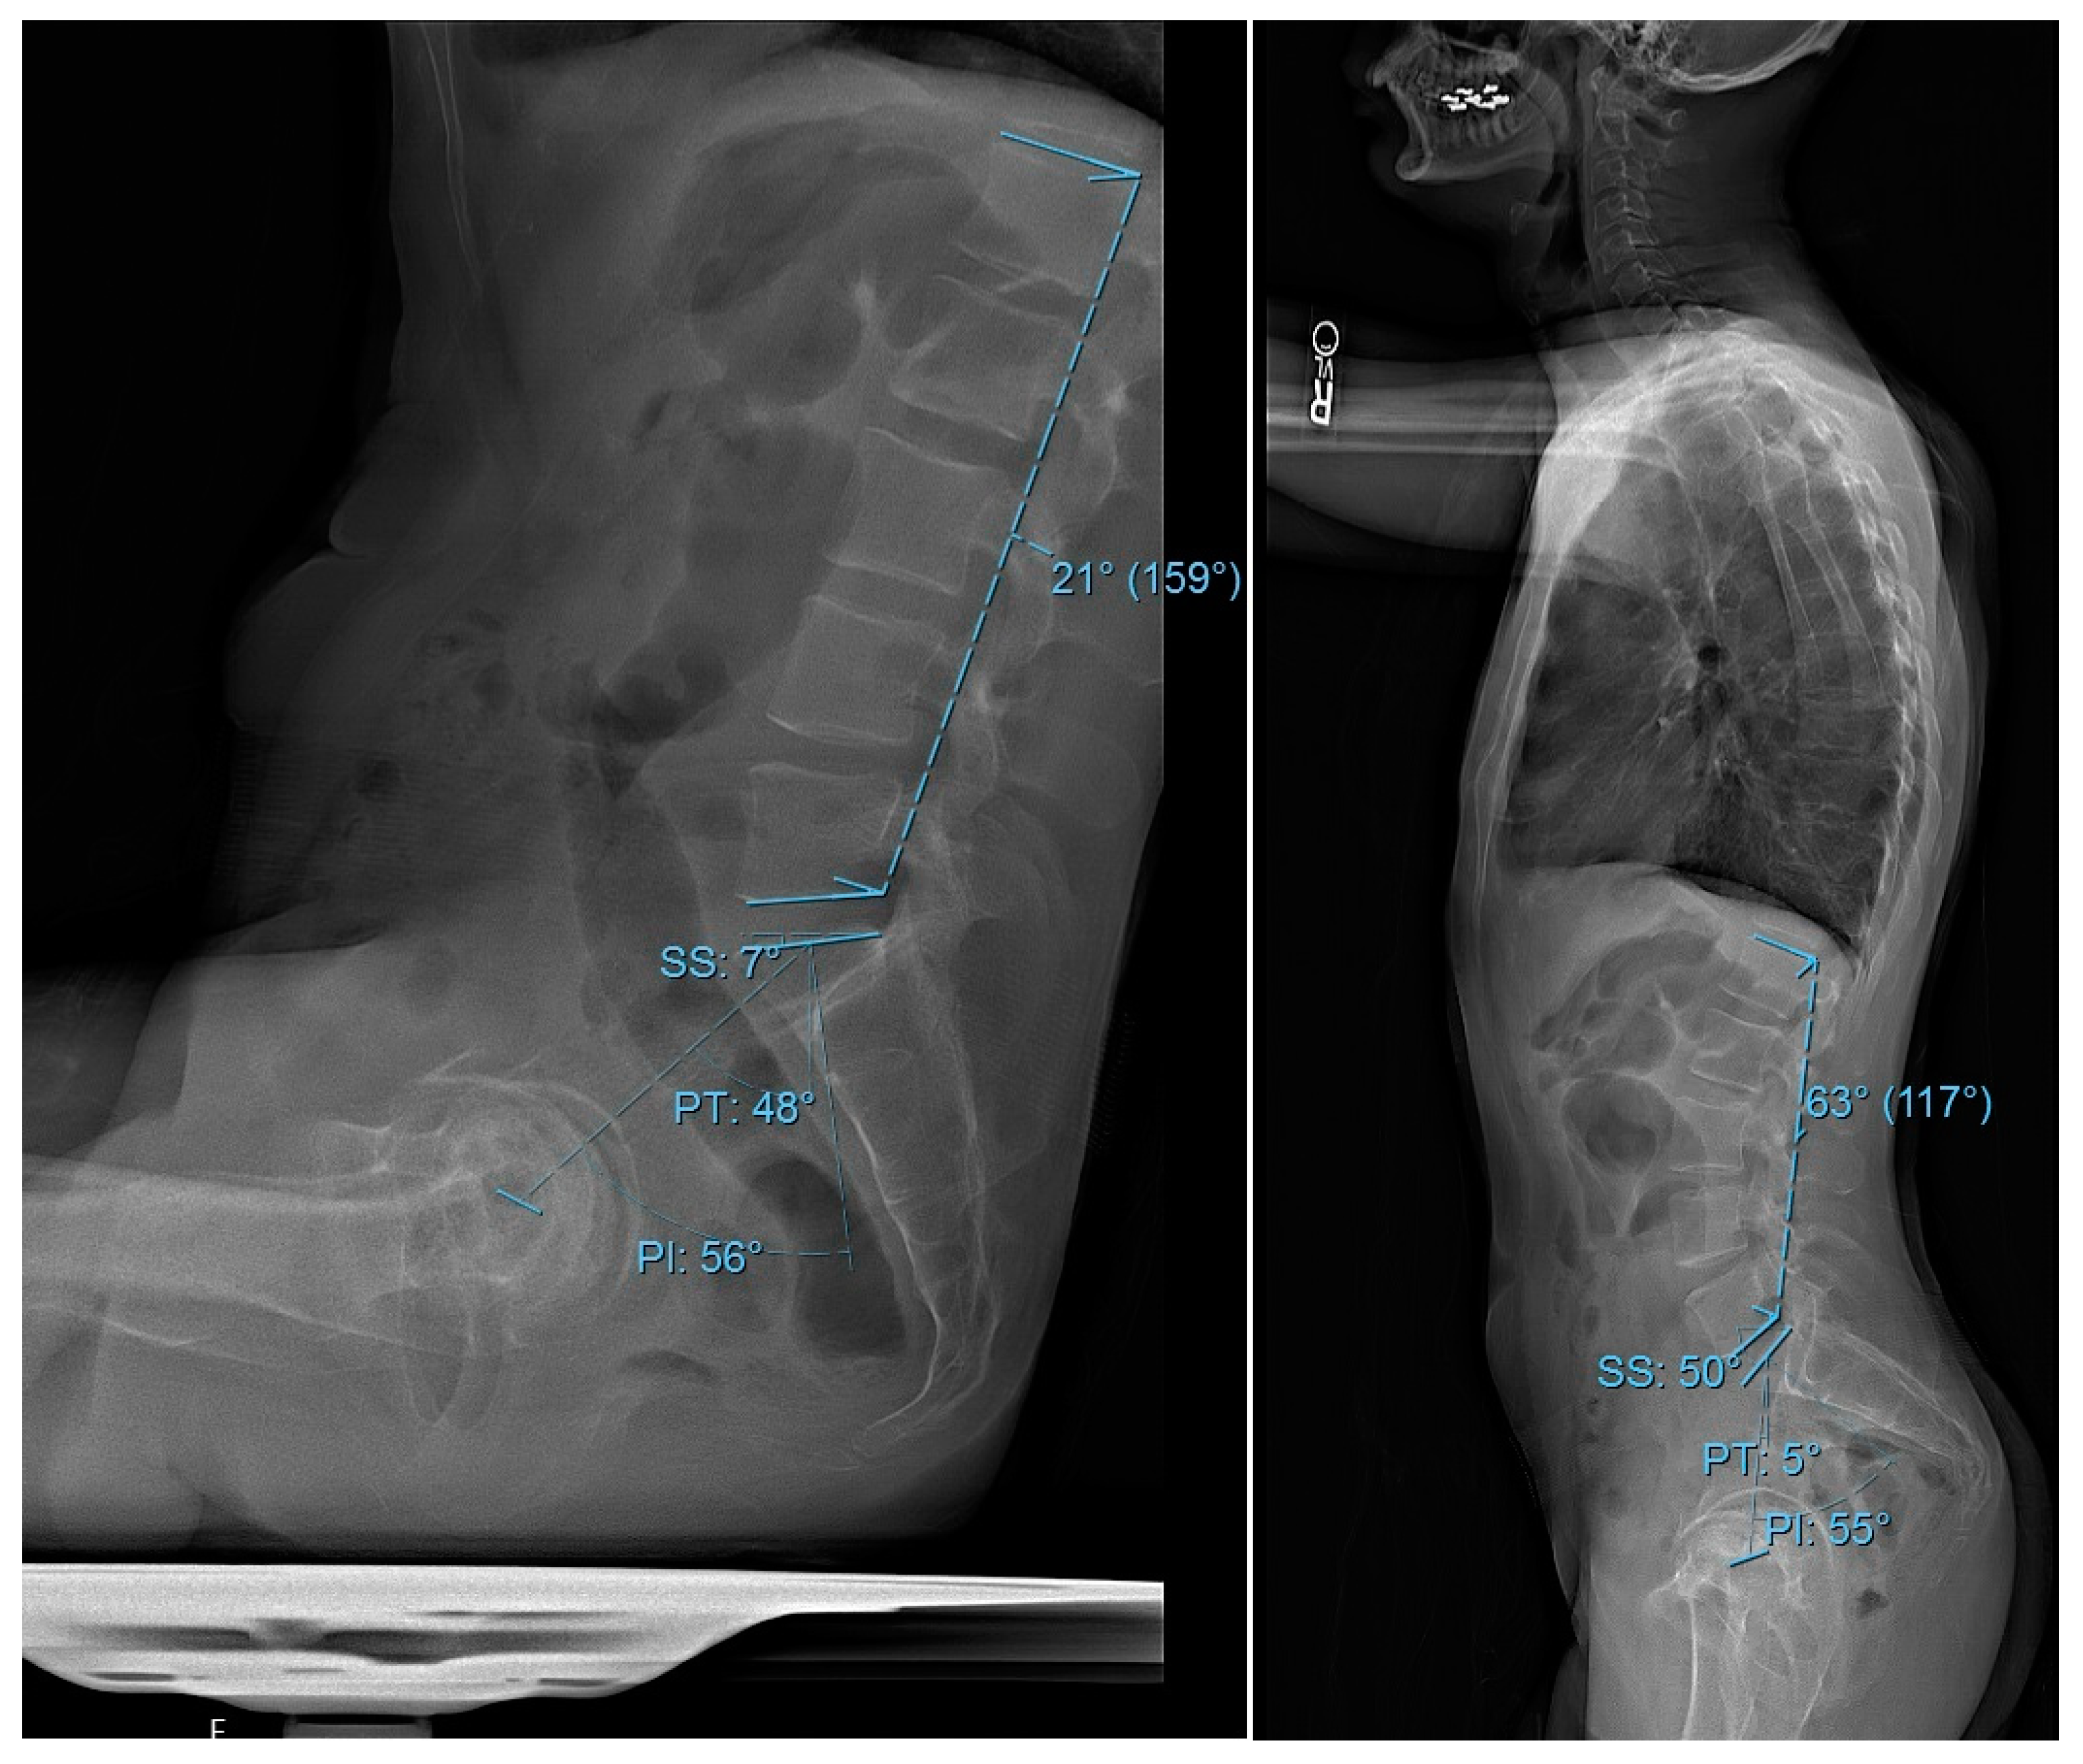

Demographic and perioperative data were collected and managed using Research Electronic Data Capture (REDCap), hosted by the Weill Cornell Medicine Clinical and Translational Science Center (New York, NY, USA) and supported by the National Center for Advancing Translational Science (NCATS) of the National Institute of Health (NIH), (Bethesda, MD, USA). The analyzed variables included demographic factors such as patient age, gender, BMI, comorbidities, and the age-adjusted Charlson Comorbidity Index (CCI). Surgical and postoperative variables encompassed the American Society of Anesthesiologists (ASA) score and date of surgery. All radiographic measurements were performed using the institutional Picture Archiving and Communication System (PACS) software (Sectra AB, Linköping, Sweden; v12.3.7). Three independent, fellowship-trained spine surgeons conducted manual measurements using standardized PACS angle and line tools. If two observers differed in measurements by more than ±5°, the radiograph was jointly reviewed and a consensus measurement was recorded for consistency and accuracy. Preoperative radiographic parameters were PI, PT, SS, LL, and PI-LL in both sitting and standing positions (Figure 1).

Figure 1. Spinopelvic measurements in sitting and standing XRs. Lateral radiographs of an idealized patient demonstrating the measurements of spinopelvic parameters. The parameters include pelvic incidence (PI), pelvic tilt (PT), sacral slope (SS), and lumbar lordosis (LL): on the left panel in sitting and on the right panel in standing.